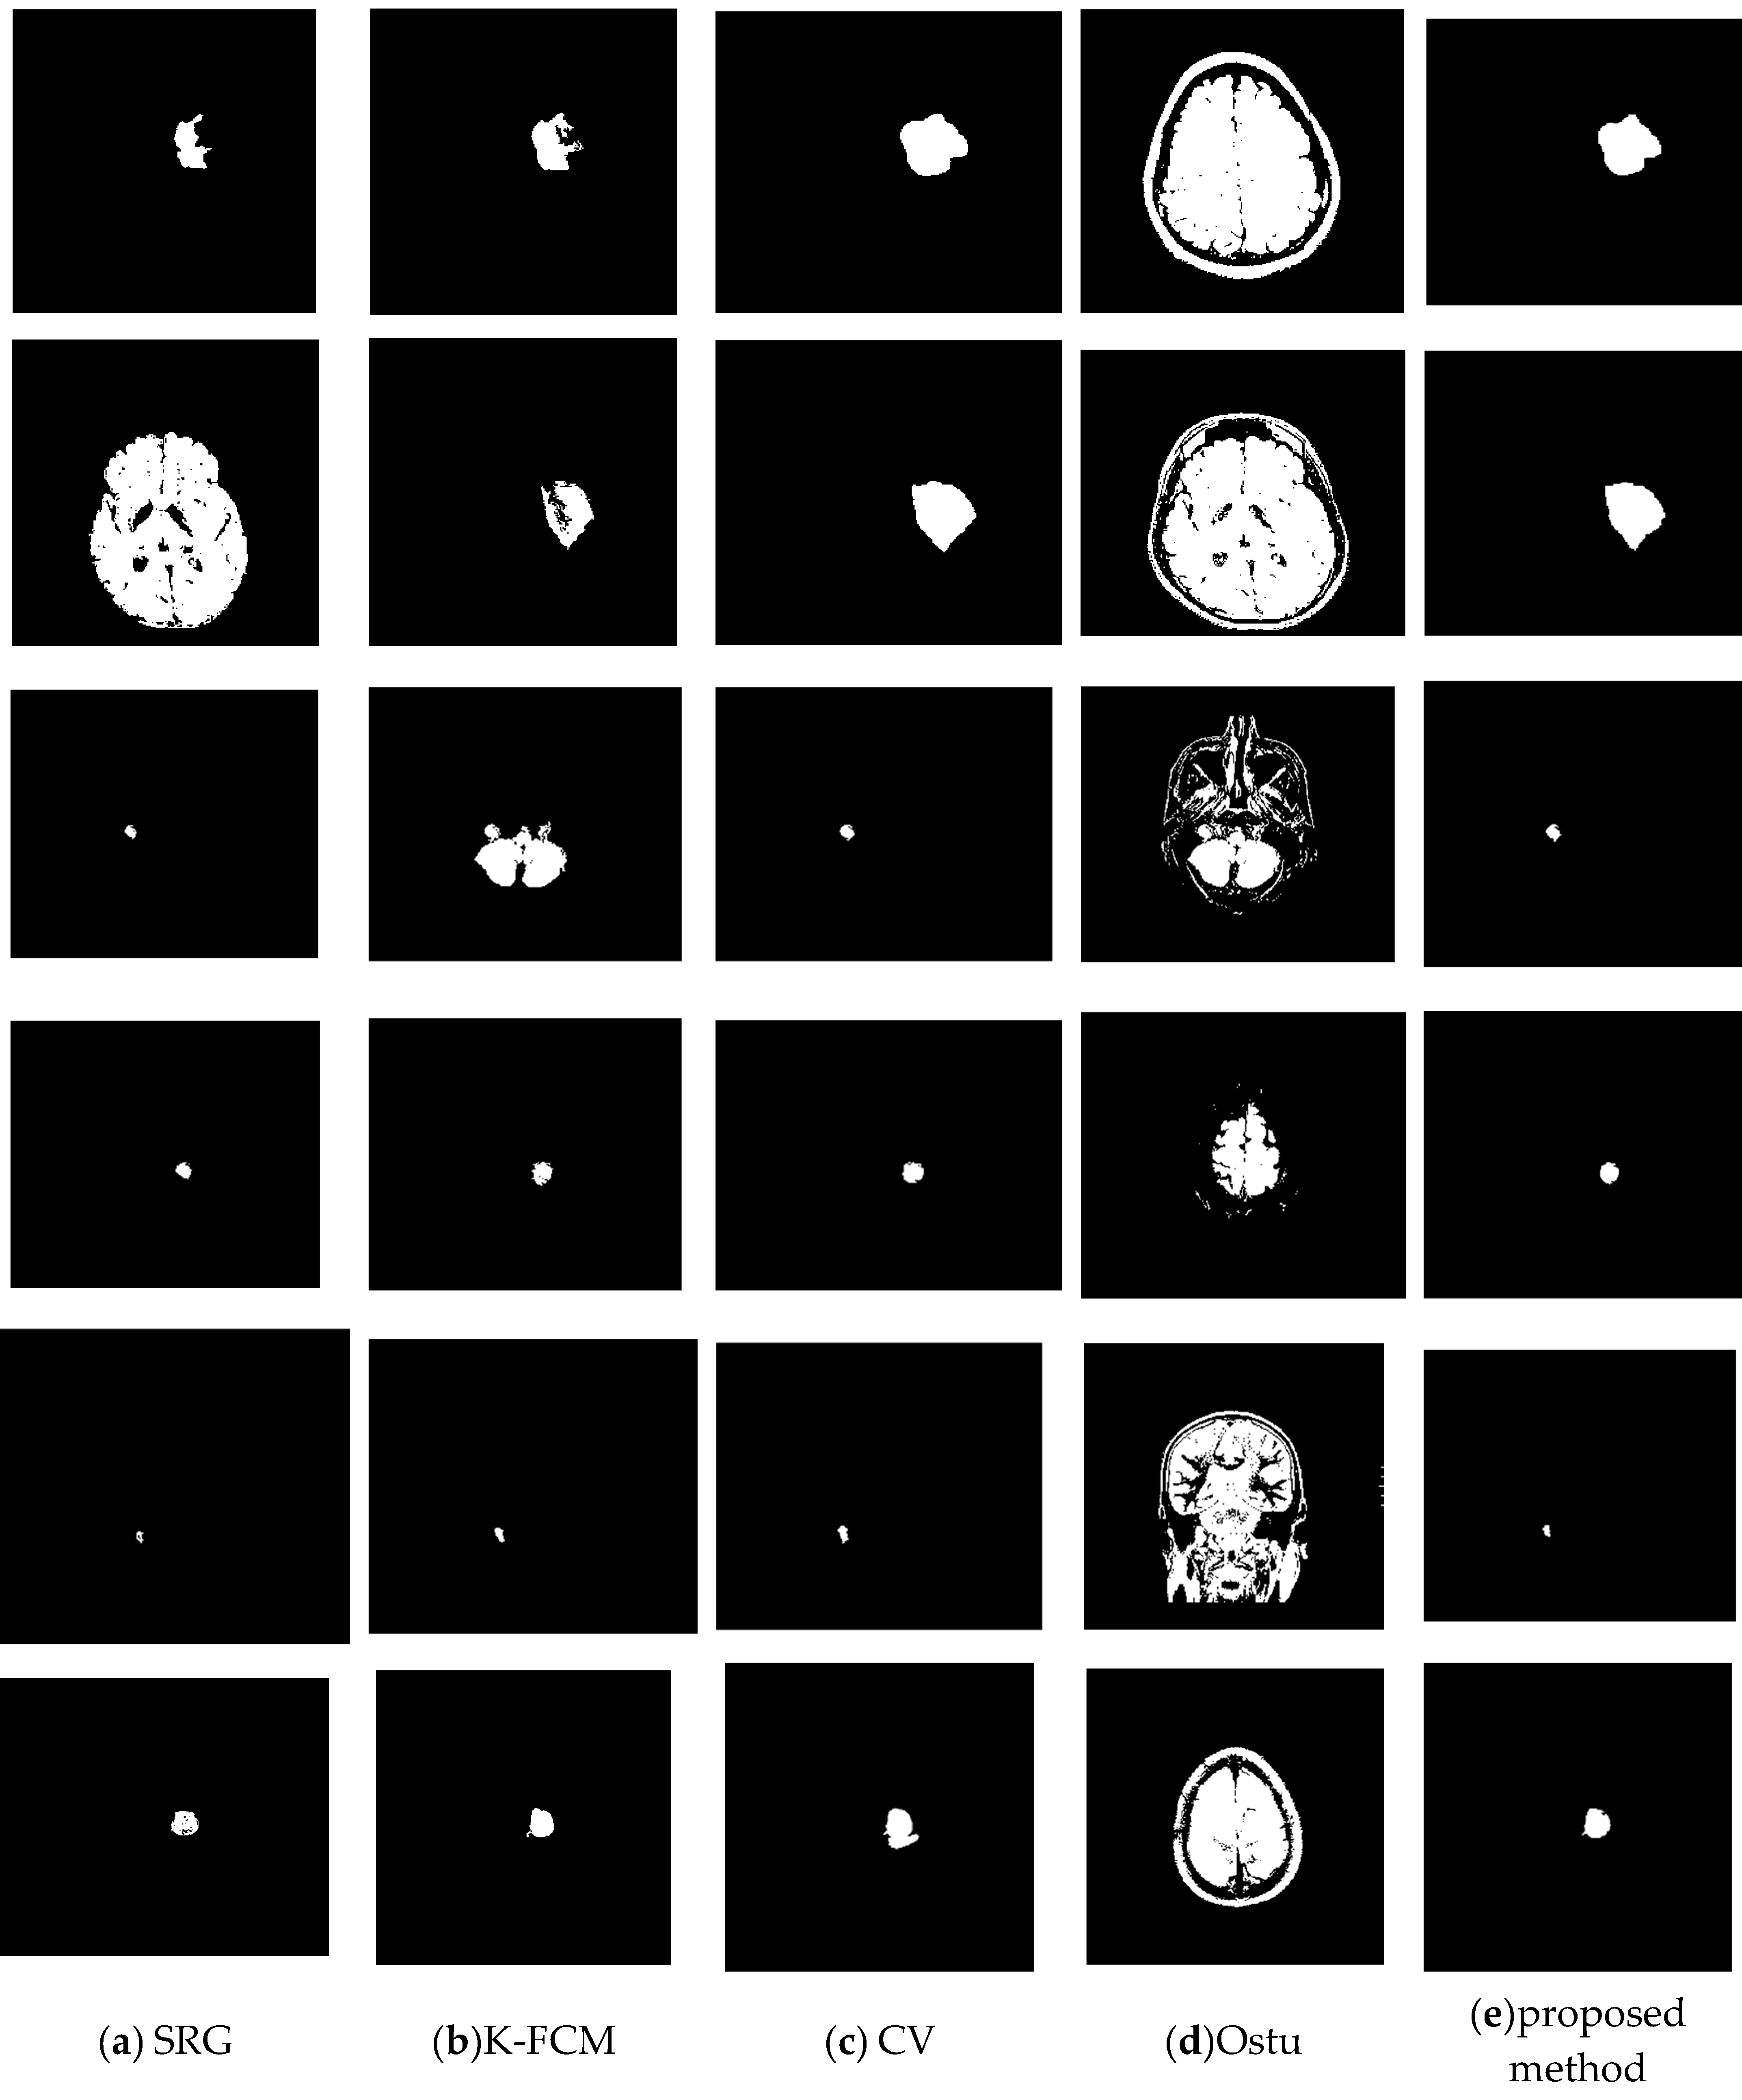

To verify the effectiveness of the proposed method, we randomly selected some images to test. For each brain tumor cross-sectional image, we compared the results of each algorithm with the results of manual segmentation. Figure 8 is the original image. Figure 9 shows the visualization results obtained by the proposed algorithm, CV, K-FCM [], Ostu [] and region growing algorithm [] for brain tumor segmentation. The experimental results of the threshold algorithm were obtained by manually adjusting the threshold parameters several times. Except for the algorithm in this paper, the other methods could not fully achieve automated detection and segmentation. From Table 2, we can observe the quantitative results of the four detection algorithms for brain tumor. When Accuracy, JSC and DSC were higher, it indicated that the prediction accuracy of the target was higher. The proposed method outperformed other algorithms on Accuracy, JSC, and DSC. Therefore, from the comprehensive analysis in Figure 9 and Table 2, it can be seen that the algorithm in this study had high accuracy in detecting and segmenting brain tumors. The proposed method has certain competitiveness compared with other classical algorithms, and is expected to provide a reliable reference for clinical decision-making. In addition, as is shown in Table 3, there are significant differences between the proposed model and other models.

Figure 8.

Examples of brain tumor images. (a) Test1. (b) Test2. (c) Test3. (d) Test4. (e) Test5. (f) Test6.

Figure 9.

Comparison of the proposed method with others. (a) SRG. (b) K-FCF. (c) CV. (d) Ostu. (e) The proposed method.